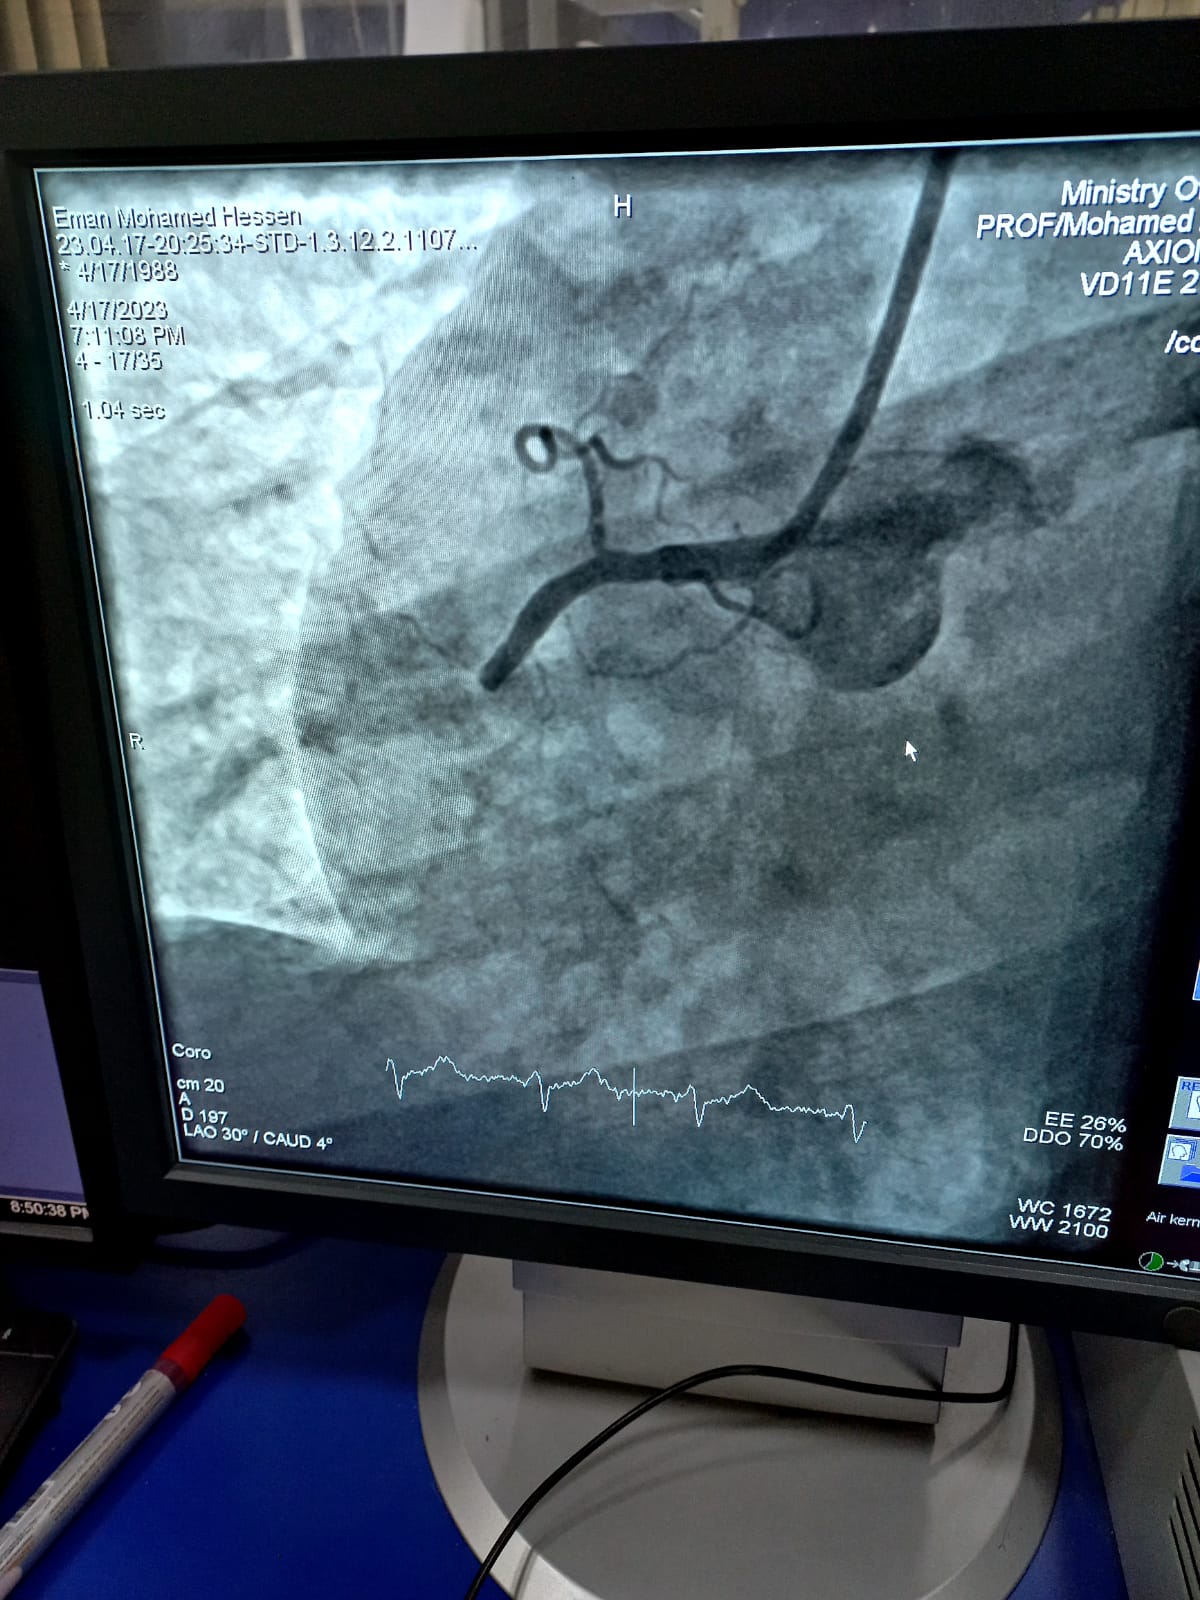

تنفيذاً لتوجيهات الدكتور خالد عبدالغفار وزير الصحة والسكان، والأستاذ الدكتور ممدوح غراب محافظ الشرقية، تعليمات الدكتور هشام شوقي مسعود وكيل وزارة الصحة بالشرقية، برفع كفاءة الخدمات الطبية المقدمة للمرضى بمستشفيات الصحة بالمحافظة، استمرارا لنجاح منظومة العلاج علي نفقة الدولة، قام الفريق الطبي بوحدة القسطرة القلبية بمستشفى الزقازيق العام، بقيادة الأستاذ الدكتور السيد فرج أستاذ القلب والمشرف الفني للقسطرة القلبية، والدكتور حسام عطية استشاري القلب ومدير وحدة القسطرة، والدكتور محمد عبدالله، والدكتور عبدالله بنداري أطباء القلب، بإجراء قسطرة قلبية عاجلة لإنقاذ حياة مريضة تبلغ من العمر ٣٥ عاماً، كانت تعاني من احتشاء بعضلة القلب ومريضة بالسكري، ولم تستجيب للعلاج الدوائي، وتم إجراء القسطرة (Rescue PCI) بنجاح حيث تبين إنسداد تام في الشريان التاجي الأيمن، وتم عمل توسعة وفتح للشريان وتركيب دعامة، والمريضة بحالة جيدة تحت الملاحظة بالعناية المركزة.